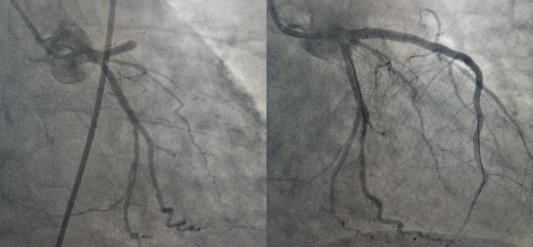

10:10患者到達(dá)延安大學(xué)咸陽醫(yī)院,剛將患者從救護(hù)車推下進(jìn)入門診大廳,患者突然出現(xiàn)意識喪失,觸摸大動脈搏動消失,心電監(jiān)護(hù)提示室性心動過速,危急時刻,延安大學(xué)咸陽醫(yī)院胸痛中心楊飛娟主治醫(yī)師、謝昕護(hù)士、王丹丹護(hù)士協(xié)同涇陽縣醫(yī)院尹夢肖主治醫(yī)師、張陽陽護(hù)士立即就地?fù)尵?,門診梁田副主任醫(yī)師及胸痛中心二線李新國主任也聞訊趕來支援。經(jīng)過3次電除顫及胸外按壓后患者恢復(fù)竇性心律,意識好轉(zhuǎn)。在場醫(yī)務(wù)人員立即將患者送至導(dǎo)管室,實(shí)施急診PCI,于10:57開通閉塞血管,恢復(fù)血流,將危在旦夕的夏大叔從鬼門關(guān)搶救回來。目前患者正在進(jìn)一步康復(fù)中。